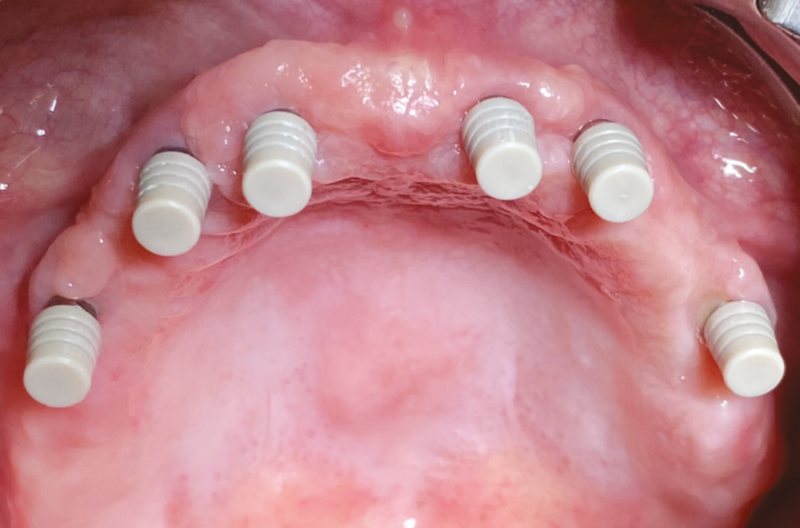

Passati 6 mesi di guarigione e di osteointegrazione, gli impianti sono stati esposti durante una seconda chirurgia, dove abbiamo avuto l’opportunità di ripartire la mucosa aderente dove mancante; in questa fase si sono sostituiti i tappi di chiusura con i tappi di guarigione affioranti nel cavo orale (Fig. 9). Passate due settimane dall’esposizione degli impianti, si procede con il rilevamento dell’impronta Implant Level che fornisce informazioni circa le posizioni e le quote implantari (Figg. 10, 11).

Fig. 9 – Inserimento di tappi di guarigione durante la seconda chirurgia di esposizione implantare ad osteointegrazione avvenuta